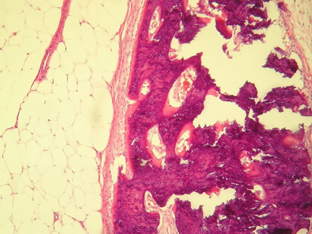

Empirical medical management with intravenous steroid (Methylprednisolone) + Ceftriaxone and Acyclovir was started. A diagnosis of autoimmune encephalitis was established without improvement in the clinical picture despite medical management, so surgical management was decided for the adnexal tumor by means of exploratory laparotomy with right salpingo-oophorectomy, reporting as a finding: right adnexal solid tumor with well-defined borders of 6 x 4 cm, pearly with intact capsule, uterus measuring 7 x 5 cm and left appendage measuring 3 x 2 cm, macroscopically normal. A transoperative study was carried out with a histopathological report of a mature cystic teratoma with a 4.7 cm long axis (Figures 5 and 6).

Figure 5 40x photomicrograph. Section stained with Hematoxylin and Eosin; Alveolar structures with simple squamous epithelium and bronchi covered by ciliated columnar epithelium are observed in the context of a Mature Teratoma.

Figure 6 20x photomicrograph. Section stained with Hematoxylin and Eosin; Adipose tissue, fibrous pseudocapsule and osteoid tissue are observed, with bone trabeculae and osteoblasts in the context of a Mature Teratoma.